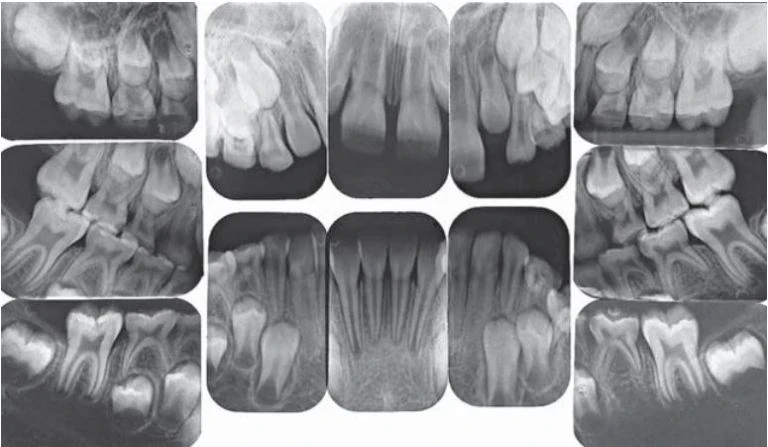

Chụp phim cho trẻ em là một vấn đề khó. Mặc dù nguyên tắc chụp phim quanh chóp cho trẻ và người lớn là như nhau nhưng trẻ lại có cấu trúc giải phẫu nhỏ và khó kiểm soát được hành vi của trẻ. Cung hàm nhỏ hơn đòi hỏi receptor quanh chóp nhỏ hơn. Khẩu cái và sàn miệng cạn đòi hỏi thay đổi việc đặt receptor.

Phim X quang răng sữa gồm hai phim vùng răng cửa, bốn phim răng nanh và bốn phim vùng răng sau và hai phim cánh cắn